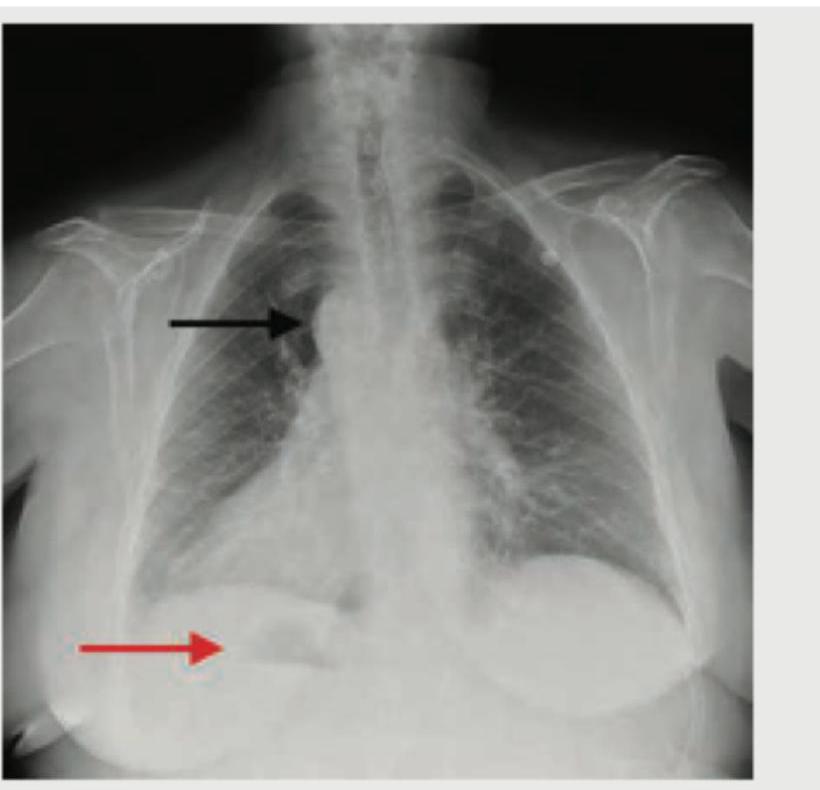

What does the following radiograph show?

Explanation: ***Correct Option: Gas under diaphragm*** - The image clearly shows a crescent-shaped lucency (gas) beneath the diaphragm, indicated by the red arrow, which is characteristic of **pneumoperitoneum**. - This finding is a critical sign of a **perforated viscus** within the abdomen, such as a perforated peptic ulcer, perforated diverticulitis, or other hollow viscus perforation. - **Free air under the diaphragm** is best seen on an erect chest X-ray or erect abdominal film and is a surgical emergency. *Incorrect Option: Bat wing sign* - The **"bat wing"** or **"butterfly" sign** refers to bilateral perihilar infiltrates seen in conditions like **pulmonary edema** due to congestive heart failure or acute respiratory distress syndrome (ARDS). - This pattern is not present in the provided image; the lung fields appear relatively clear except for the presence of gas under the diaphragm. *Incorrect Option: Situs inversus* - **Situs inversus** is a congenital condition where the major visceral organs are reversed or mirrored from their normal positions, manifesting as the **heart shadow** on the right side and liver on the left side. - The image shows the heart on the normal left side, and there is no evidence of reversed organ positioning. *Incorrect Option: Money bag appearance* - The **"money bag appearance"** is a recognized radiological sign seen in conditions like **hydronephrosis** on intravenous pyelogram (IVP) or in **hiatal hernia** where the gastric fundus appears as a rounded sac above the diaphragm. - This finding is not demonstrated in the provided image, which clearly shows free gas beneath the diaphragm rather than a soft tissue mass or fluid-filled structure.